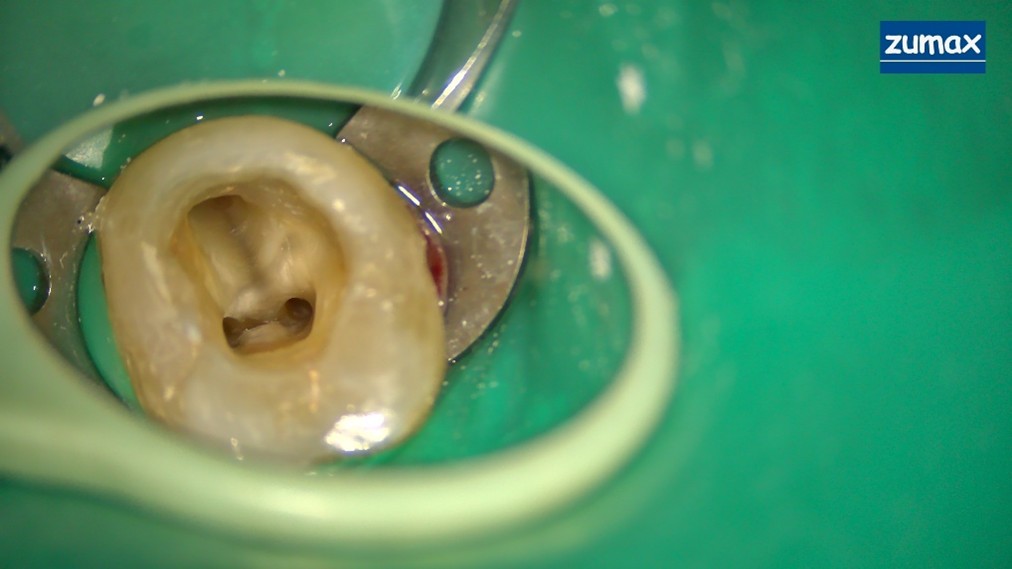

Clinical Case Study: Microscope-Assisted Root Canal Treatment of Tooth 37

Patient History

A 38-year-old Indian male visited our clinic with a complaint of toothache in the lower left back tooth region.

The pain started a few weeks ago and had progressively worsened. It was continuous and throbbing in nature, with a history of nocturnal pain. The patient reported temporary relief after taking painkillers.

Clinical Examination

On examination, deep caries was noted on distal 37.

A periapical radiograph was taken, and treatment options were discussed. The patient agreed to undergo endodontic therapy for tooth 37.

The Challenges in This Case

• 1.Limited mouth opening, making access difficult

• 2.Variable root canal anatomy

• 3.Difficulty in sealing the coronal portion of the tooth, especially the distal margin

Microscope Advantages in This Case

MICROSCOPIC PICTURE :

MESIAL CANALS

MESIAL AND DISTAL CANALS

The dental operating microscope provided significant advantages during treatment:>

• 1.Better visualization helped reduce excessive dentin removal

• 2.Confirmation of complete pulp chamber debridement

• 3.Improved ability to locate the canals

Treatment Procedure and Radiographic Documentation

Radiographs and clinical pictures were taken during treatment, including:

• Master cone GP periapical radiograph

• Post-operative X-ray

• Microscopic images of mesial canals

• Microscopic images of mesial and distal canals

• Images captured during the obturation step

After obturation, the tooth was fully restored with composite. The patient is yet to receive a crown.